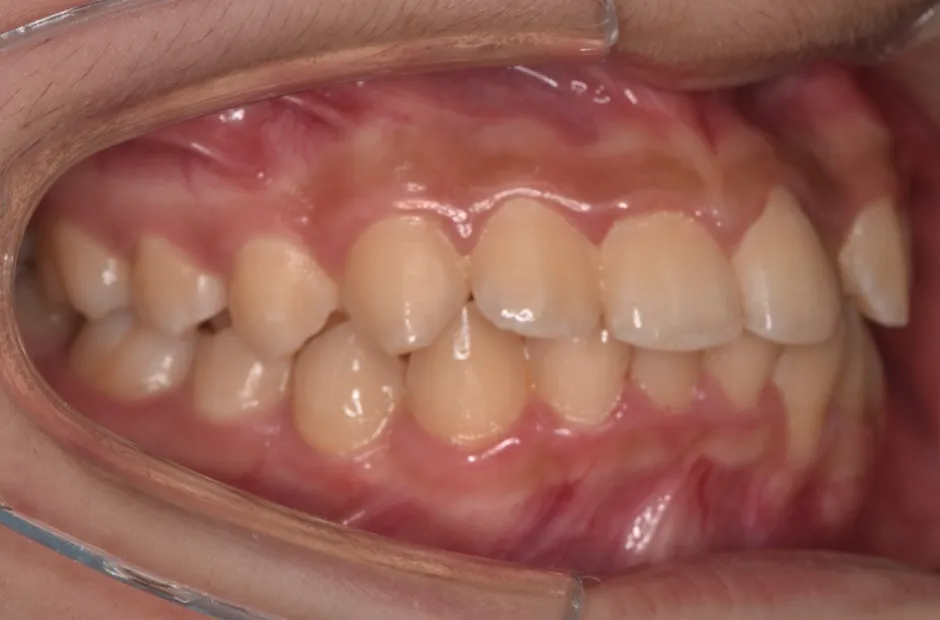

ブラケット矯正

前歯部反対咬合

| 診断名・主訴 | 前歯部反対咬合 |

|---|---|

| 年齢・性別 | 14歳・男性 |

| 治療期間・回数 | 1年2か月 |

| 治療に用いた主な装置 | ブラケット矯正 |

| 抜歯部位 | なし |

| 治療費 | 60万円(税抜) |

| リスク・副作用 | 装置による違和感・疼痛・歯肉退縮・歯根吸収・虫歯のリスクなど |

治療後